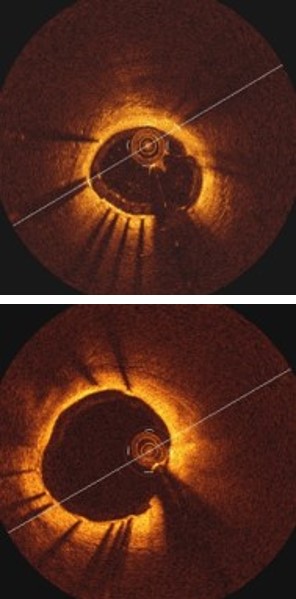

Refer to caption

(a) Image

(b) Labels

(c) F-RCNN

(d) Hong.

(e) Hyeong.

(f) Ours

Figure 4: Comparison of our detection results with existing comparison methods

Table 1 and Fig. 3(a) illustrate our method achieved the overall best performance when compared to the existing methods for strut detection. The traditional methods (Hyeong et al.[7], Hong et al.[5] and Ancong et al.[13]) using hand-crafted features with conventional classifiers achieved competitive performance when compared with Faster-RCNN method. Fig. 4(d) and Fig. 4(e) show two example results where both Hyeong et al and Hong et al methods fail to detect strut points where there is low-contrast to the background. In contrast, Faster-RCNN has the ability to combine deep semantic information and shallow appearance information in a hierarchical manner that enables it to encode image-wide location information and semantic characteristics. However, Faster-RCNN lacks constrain of the overall appearance of all the struts. Consequently, Faster-RCNN generates poor detection results for small struts (as shown in Fig. 4(c)).